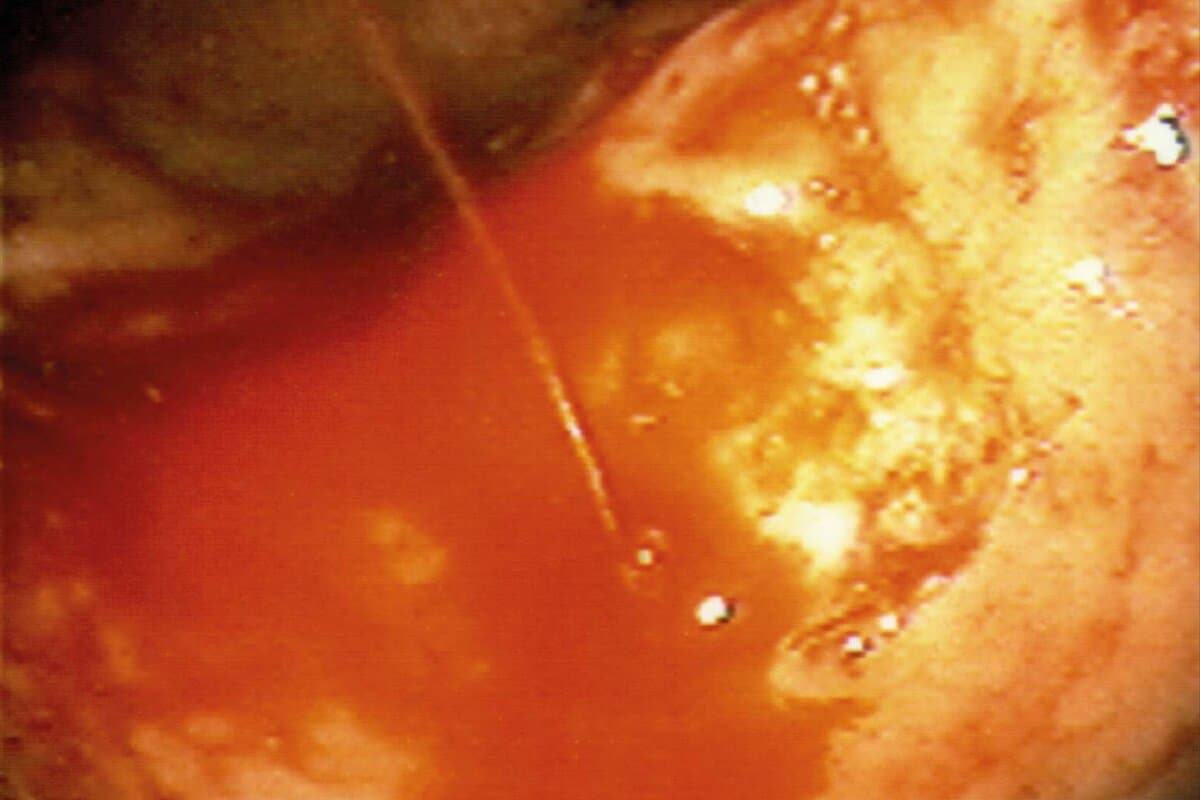

Endoskopisch lässt sich die nichtvariköse Blutung anhand der Forrest-Kriterien klassifizieren, um das Risiko einer Rezidivblutung einschätzen zu können. Während der Untersuchung sollen thermische und mechanische Verfahren sowie gegebenenfalls zusätzliche Injektionstherapien die Blutung stoppen. Over-the-Scope-Clips werden speziell bei Ulkusblutungen empfohlen. Im Fall von Varizen wird eine medikamentöse Therapie kombiniert mit Ligatur empfohlen. Bei refraktärer Blutung ist als vorübergehende Versorgung ein Metallstent angezeigt. Bleiben diese erfolglos, gelten Sengstaken-Sonde im Ösophagus und Linton-Nachlas-Sonde im Bereich des Magenfundus als Alternativen. Bei Hochrisikopatienten wird auch die Anlage eines portosystemischen Shunts (TIPSS) empfohlen.

Unteren gastrointestinalen Blutungen liegen im Alter oft Divertikel zugrunde. Solche Blutungen sistieren oft spontan. Falls nicht, können sie endoskopisch mithilfe von Injektionsverfahren und/oder per Bandligatur bzw. Clipapplikation therapiert werden.